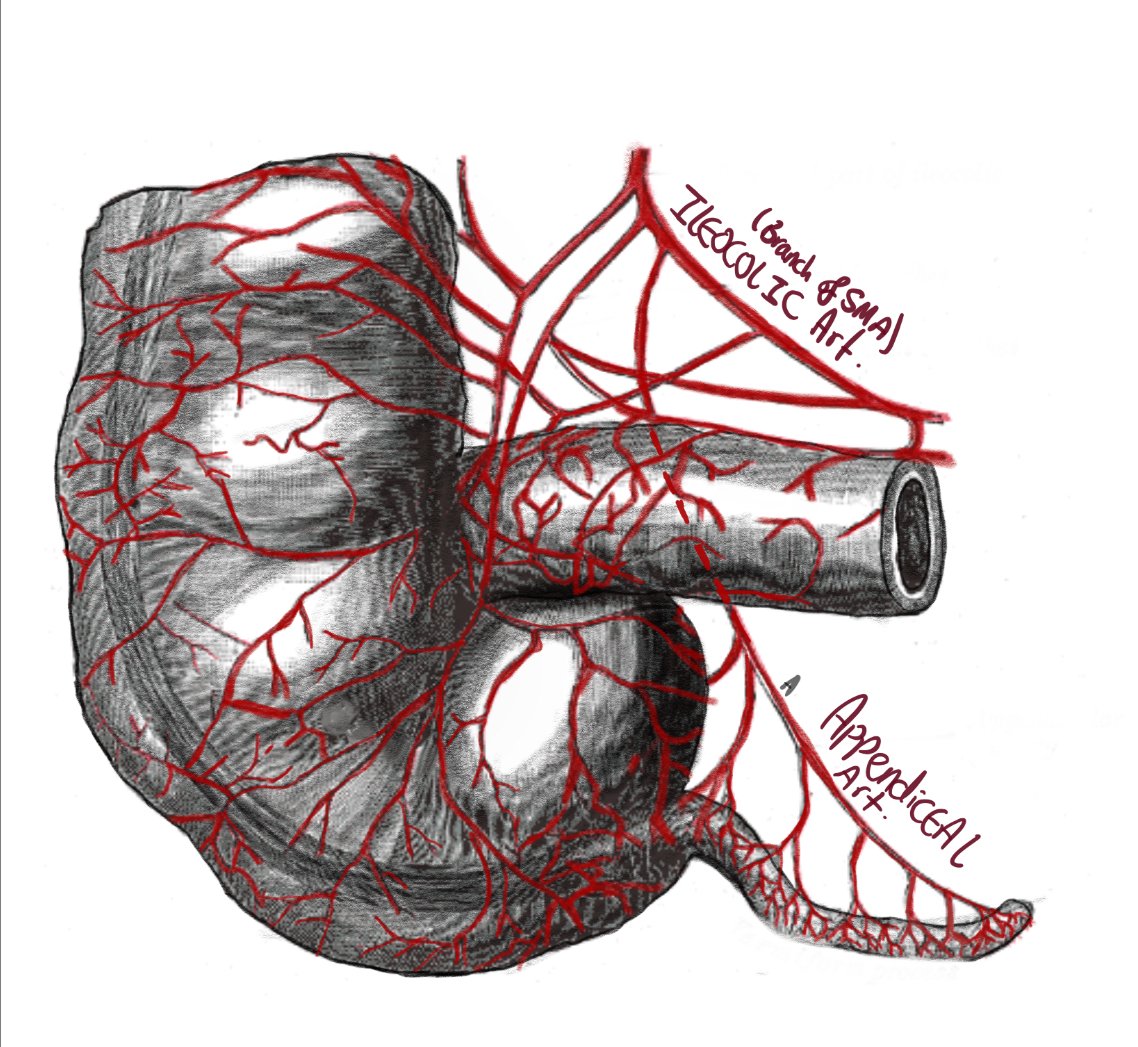

- Appendiceal artery: Branch of the ileocolic artery

- The appendix is supplied by a single artery.

- In appendicitis, due to inflammation, the intraluminal pressure will exceed the perfusion pressure resulting in ischemic injury. This ischaemia predisposes to perforation.

- On the other hand the gallbladder is supplied by the cystic artery AND the liver bed, so even if the cystic artery is compromised, it will still get some blood supply through the liver bed.

Blood Supply And Lymph Drainage

Arterial Supply

Abdominal aorta

Superior mesenteric artery (SMA)

ileocolic artery

appendiceal artery

Location: Contained in the mesoappendix

Characteristics: End artery, usually solely supplies the appendix

Remember: The appendix is a structure of the midgut, so it’s supplied by a branch of the SMA.

Diagram depicting the ileocolic artery and the appendicular artery supplying the appendix and the terminal ileum.

Clinical Relevance: Appendiceal Perforation vs. Gallbladder Perforation

Why is appendiceal perforation very common in appendicitis, but a perforated gall bladder is a much less common occurrence?